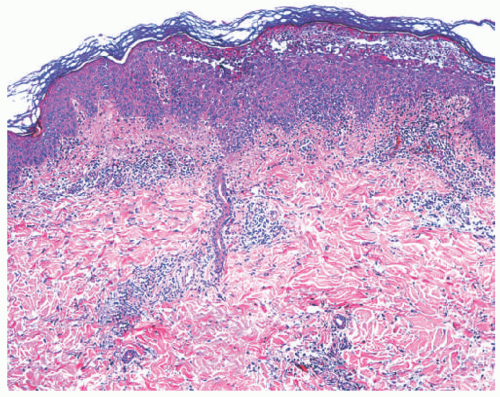

Histologic Findings

Histologically, erysipelas is characterized by marked subepidermal edema, and a diffuse, variably dense interstitial infiltrate of neutrophils in the underlying dermis, without abscess formation.10 The infiltrate is accentuated around blood vessels, and nuclear dust may be present. Capillary and lymphatic vessels may be dilated, and granulation tissue may be located beneath the zone of papillary edema as the disease subsides.

Clinically, presentation is an acute onset of fever, chills, and malaise and the subsequent appearance of a red, shiny, warm, tender plaque on a leg or the face. Histologically, one sees edema of the papillary dermis and a diffuse interstitial dermal infiltrate of neutrophils.